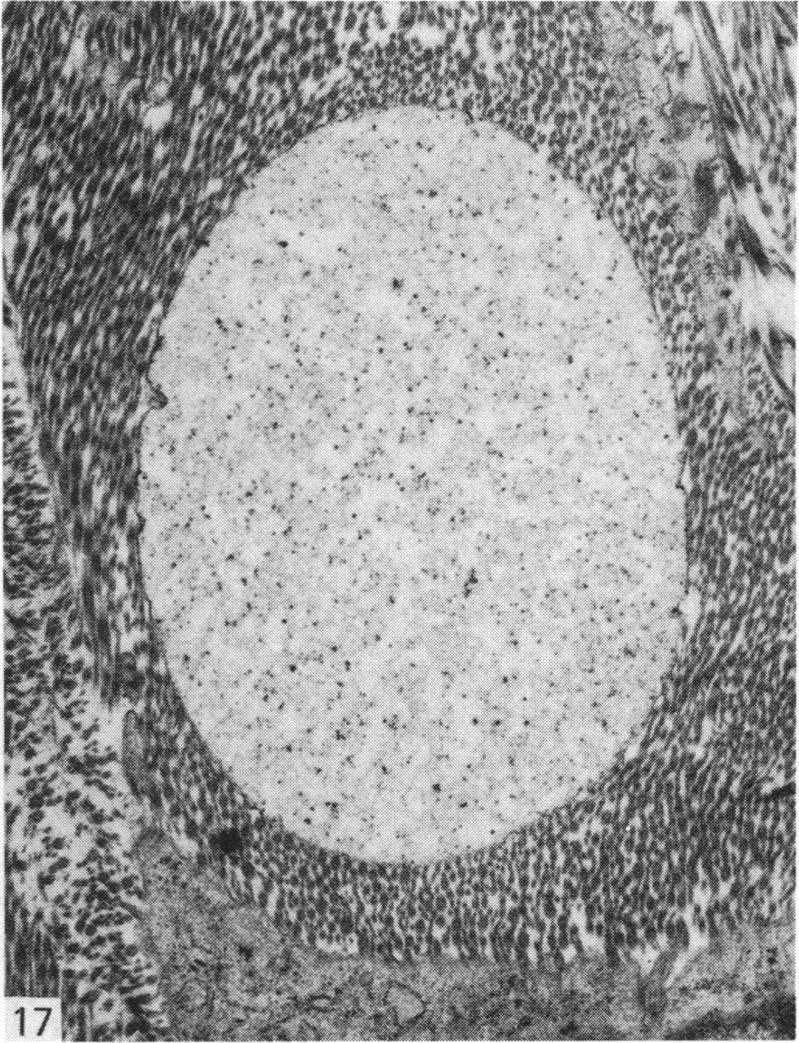

Normal human menisci obtained at autopsy (seven cases) and the injured and uninjured portions of torn menisci obtained at surgery (nine cases) were studied with the electron microscope. The surface of menisci is composed of collagen fibrils surmounted by an electron-dense surface coat. Most of the cells in menisci are chondrocytes but a few fibroblasts and cells of an intermediate form difficult to classify as either fibroblasts or chondrocytes also occur. Mast cells are found at the vascularised periphery of the meniscus. Myofibroblasts were found in the injured portions of menisci in three out of the nine cases studied. A territorial matrix containing fibrils and proteoglycan particles with associated filaments is seen around or adjacent to chondrocytes, but sometimes this matrix is sparse or absent. The interterritorial or general matrix comprises collagen fibrils of widely varying diameters (25-180 nm) set in a sparse interfibrillary matrix containing proteoglycan particles. A few mature elastic fibres and several small or immature elastic fibres and collections of electron-dense filaments are seen in the general matrix. Also seen in this region are calcified bodies and matrical lipidic debris derived by the shedding of cell processes and in situ necrosis of cells. Other features seen in the matrix of the injured portion of the meniscus include: (1) membrane-bound cystic structures; (2) parting and fraying of collagen fibrils; and (3) pools of proteoglycan particles.

对尸检获得的正常人类半月板(7例)以及手术中获得的撕裂半月板的损伤和未损伤部分(9例)进行了电子显微镜研究。半月板表面由胶原纤维组成,其上方有一层电子致密的表面涂层。半月板中的大多数细胞是软骨细胞,但也有一些成纤维细胞以及难以归类为成纤维细胞或软骨细胞的中间形态细胞。在半月板血管化的周边发现了肥大细胞。在所研究的9例中,有3例在半月板的损伤部分发现了肌成纤维细胞。在软骨细胞周围或附近可见到一个含纤维和蛋白聚糖颗粒以及相关细丝的区域基质,但有时这种基质稀疏或不存在。区域间或一般基质由直径差异很大(25 - 180纳米)的胶原纤维组成,这些纤维分布在含有蛋白聚糖颗粒的稀疏纤维间基质中。在一般基质中可见到一些成熟的弹性纤维、几条小的或不成熟的弹性纤维以及电子致密细丝的聚集物。在该区域还可见到钙化小体以及由细胞突起脱落和细胞原位坏死产生的基质脂质碎片。在半月板损伤部分的基质中还可见到其他特征:(1)膜结合的囊性结构;(2)胶原纤维的分离和磨损;(3)蛋白聚糖颗粒池。